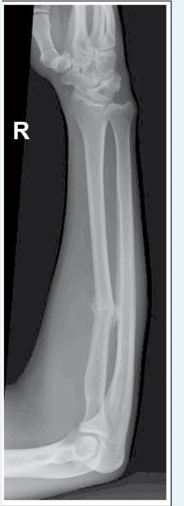

What positioning error is demonstrated on this AP forearm image?

a.Hand is pronated

b.Hand is supinated

c.Wrist and elbow are not on the same plane

d.CR is angled 5 degrees cephalad

A

How well did you know this?

1

Not at all

2

3

4

5

Perfectly

23

Q

Which projection of the forearm requires that the elbow be flexed 90 degrees?

a.Lateral with a 35 degree CR toward the shoulder

b.AP oblique, lateral rotation position

c.AP trauma imaging

d.Lateral